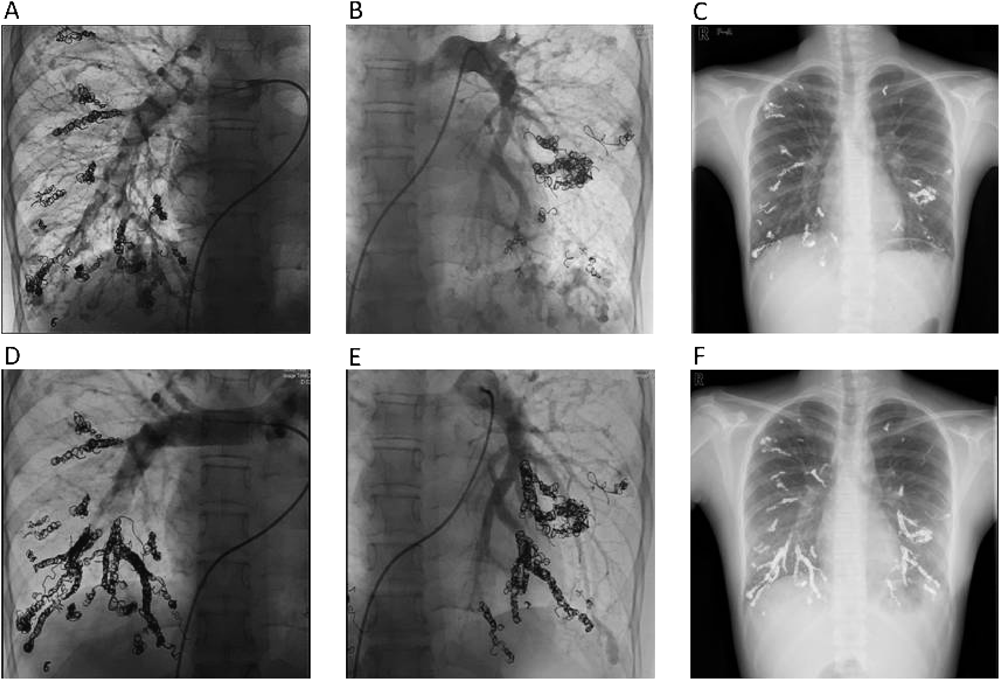

正常肺組織を犠牲にすることを前提としてコイル塞栓術を施行した両側肺全区域びまん性肺動静脈瘻の1例A Case of Diffuse Pulmonary Arteriovenous Malformationss Successfully Treated by Percutaneous Transcatheter Embolization with Sacrifice of Normal Pulmonary Arteries